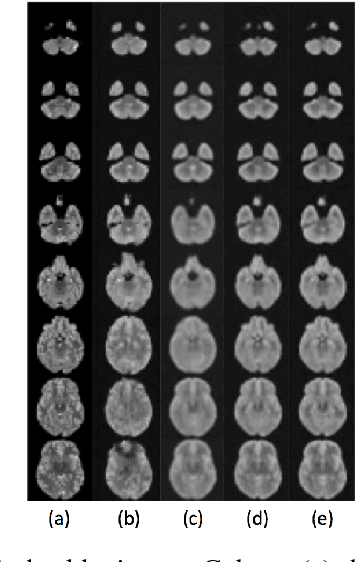

Abstract:Probabilistic modelling has been an essential tool in medical image analysis, especially for analyzing brain Magnetic Resonance Images (MRI). Recent deep learning techniques for estimating high-dimensional distributions, in particular Variational Autoencoders (VAEs), opened up new avenues for probabilistic modeling. Modelling of volumetric data has remained a challenge, however, because constraints on available computation and training data make it difficult effectively leverage VAEs, which are well-developed for 2D images. We propose a method to model 3D MR brain volumes distribution by combining a 2D slice VAE with a Gaussian model that captures the relationships between slices. We do so by estimating the sample mean and covariance in the latent space of the 2D model over the slice direction. This combined model lets us sample new coherent stacks of latent variables to decode into slices of a volume. We also introduce a novel evaluation method for generated volumes that quantifies how well their segmentations match those of true brain anatomy. We demonstrate that our proposed model is competitive in generating high quality volumes at high resolutions according to both traditional metrics and our proposed evaluation.